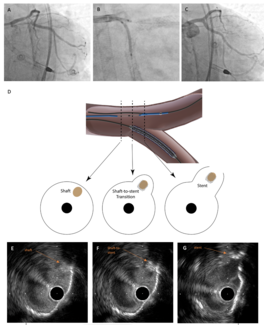

A 72-year-old woman with diabetic nephropathy was admitted for non-ST segment elevation myocardial infarction. She had undergone percutaneous coronary intervention to the ostial left anterior descending and left circumflex arteries 2 years...

Video Supplement to "Real-Time IVUS-Guided Minimal CRUSH for Bifurcation Stenting: The IM-CRUSH Technique" (Clinical Image).